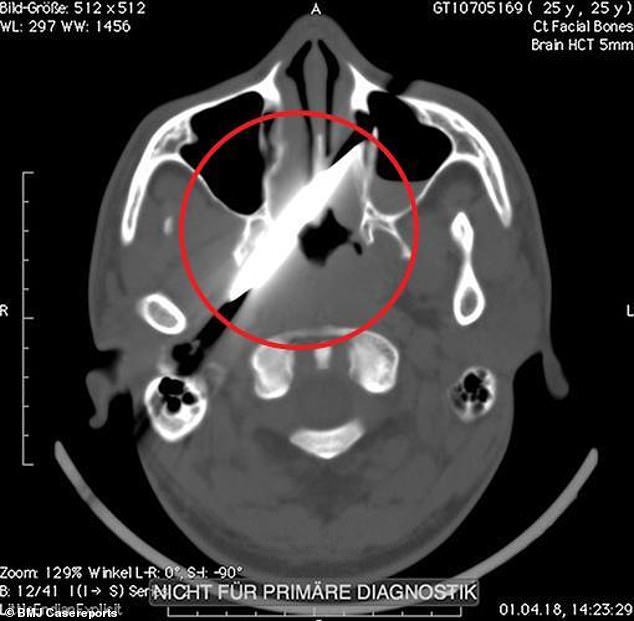

Janë fotografi që flasin vetë, ato të publikuara në revistën shkencore “British Medical Journal Case Report”. Radiografitë e tmerrshme tregojnë një burrë të cilit i është ngulur një thikë prej 10 centimetrash mes përmes fytyrës.

Mjekët shpjeguan se si thika kishte ngelur në një kockë, ku kishte qëndruar e bllokuar për katër ditë. Nga ana e tij pacienti iu tha mjekëve të Chris Hani Baragwanath Academic Hospital, se ndjente vetëm dhimbje koke dhe se nuk mund të lëvizte syrin e majtë.